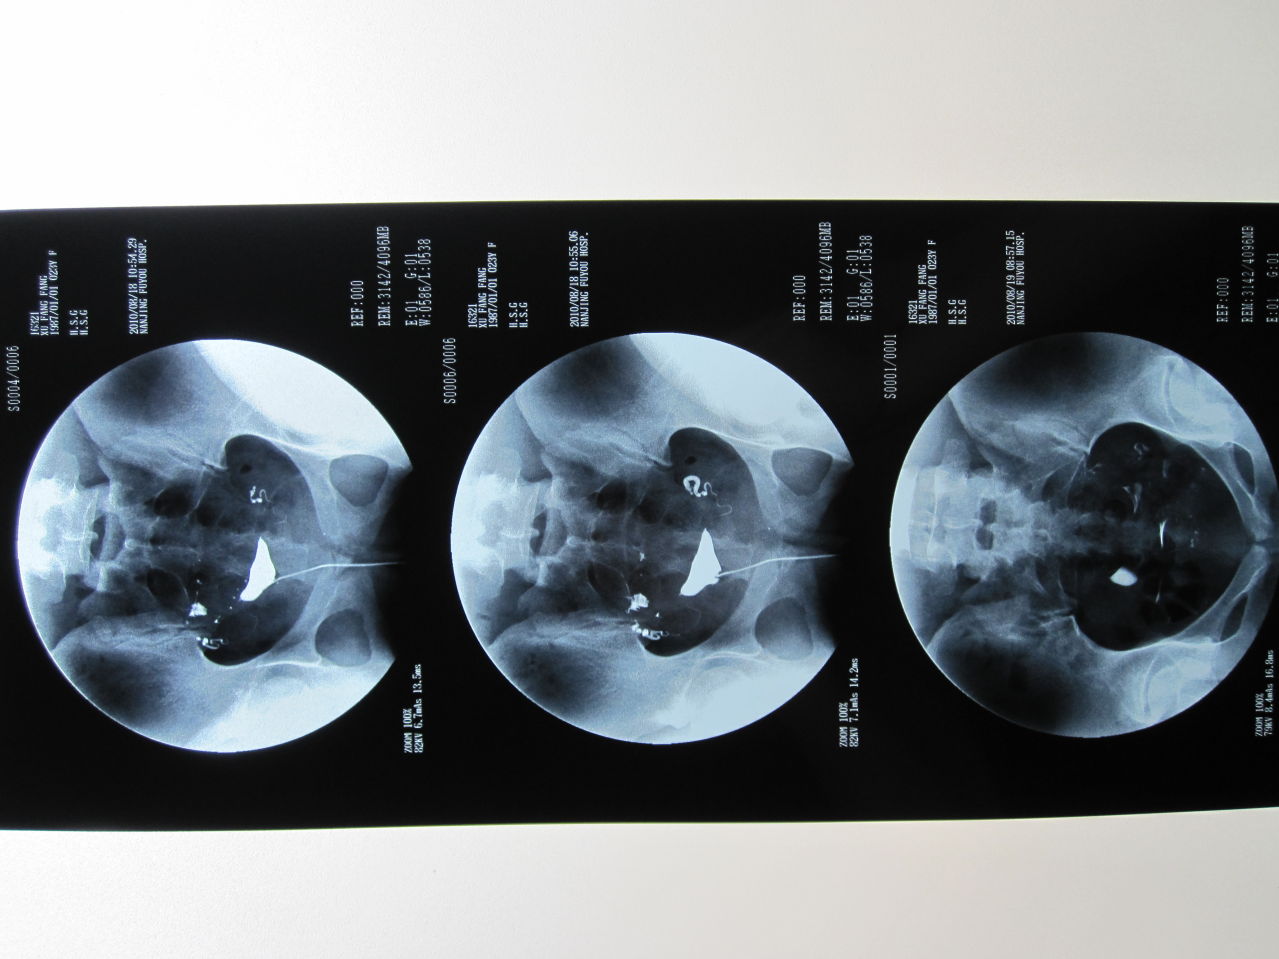

乔春艳对输卵管造影片的解析

图片尺寸1861x1240